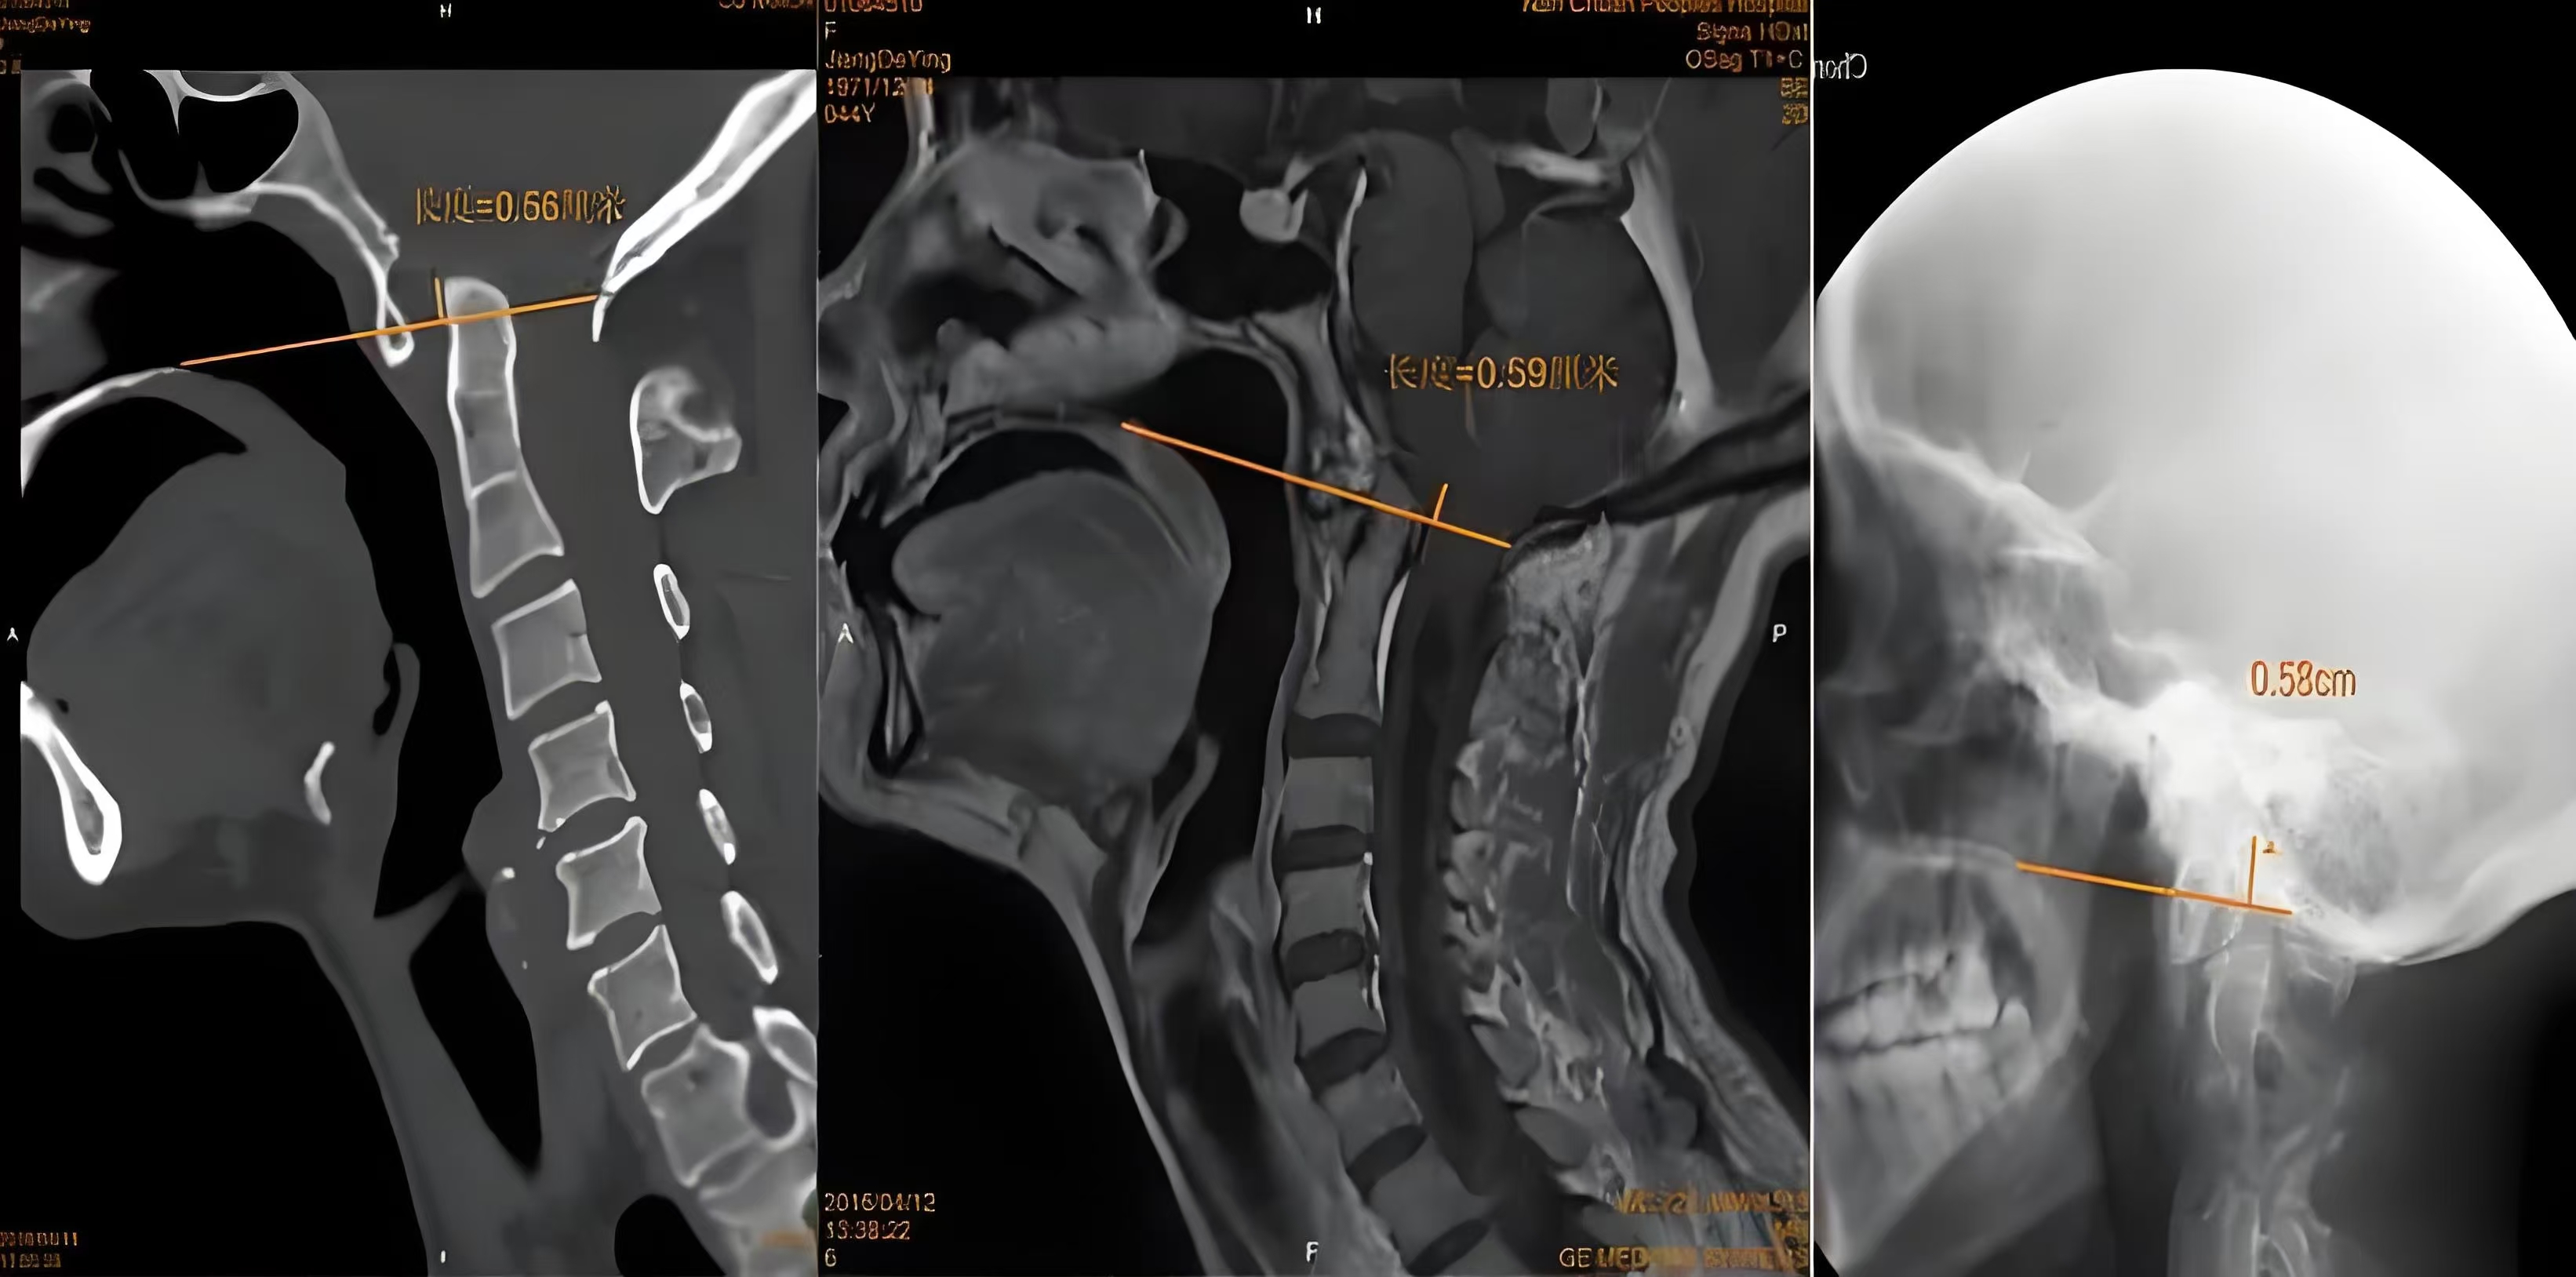

1.颅骨平片

利用颅骨平片诊断颅底凹陷需要进行各种测量,由于枕骨大孔区局部正常解剖变异较大,尽管测量方法较多,但还没有一种理想的方法对诊断本病十分可靠,因此,至少需要根据以下方法2种明显异常的测量结果才能做出诊断。

2.CT扫描

主要是显示脑组织及脑室的改变,有时可行脑室造影CT扫描,在脑室内注入非离子水溶性造影剂后行CT扫描,可观察到脑室大小,中脑水管是否通畅及第四脑室及脑干的改变,并可勾画出小脑扁桃体下缘的位置。

3.MRI检查

MRI是诊断本病最好的检查手段之一,尤其在矢状位可清楚的显示中脑水管,第四脑室及脑干的改变,小脑扁桃体下疝的程度及颈髓受压的情况,便于决定手术治疗方案。